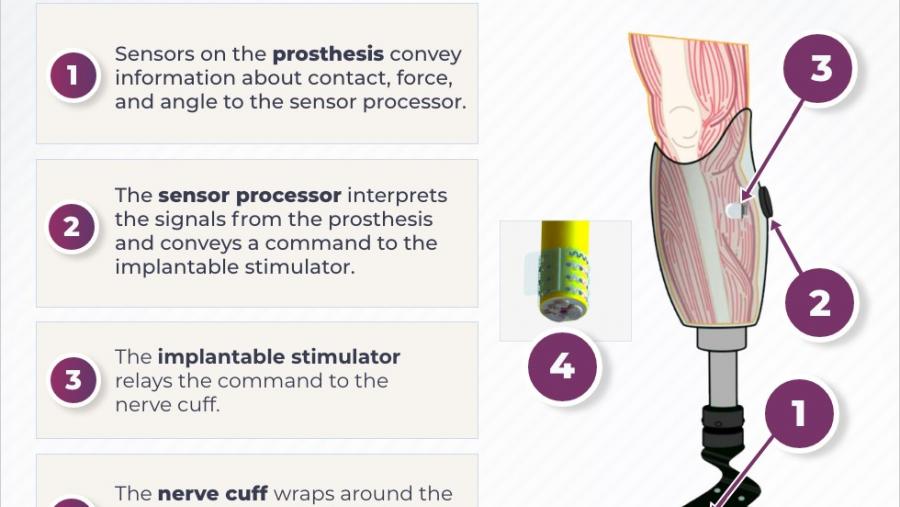

Finding the Best Treatment for Individual Patients

Published: September 27, 2023